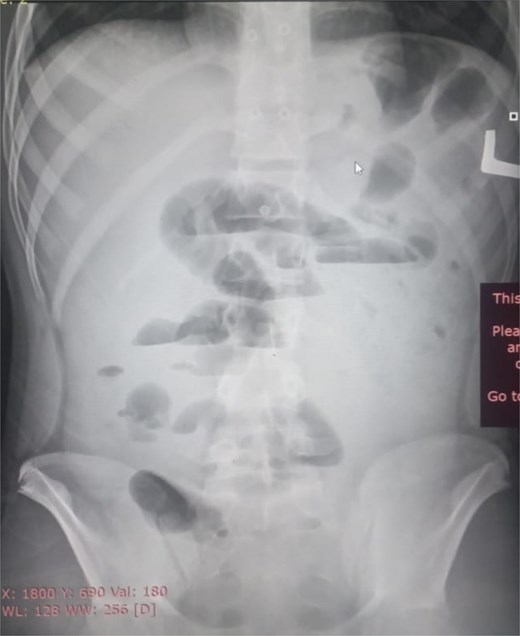

Initial radiographic evaluation with a plain abdominal X-ray confirmed the clinical suspicion of acute intestinal obstruction, demonstrating multiple air-fluid levels and diffuse small bowel dilatation (Fig. 1). To further delineate the underlying etiology, a contrast-enhanced computed tomography (CECT) scan was performed; providing critical diagnostic information it revealed, in the right iliac fossa, a striking encapsulation of the small intestine loops within a sac-like membrane, accompanied by ascites. This constellation of findings formed a pathognomonic cocoon-like structure (Fig. 2). Furthermore, the CECT identified a concurrent gut malrotation, evidenced by a left-sided displacement of the colon (Fig. 3). Laboratory findings showed an elevated total leukocyte count (TLC) of 21 000, indicative of inflammation, while other parameters were within normal limits. The patient underwent an exploratory laparotomy. Intraoperatively, the abdominal viscera were encased within a thick fibrous membrane (Fig. 4), containing ascitic fluid. The membrane was incised, adhesiolysis was performed, and the entrapped small bowel loops were released, and then a kink in the small intestine causing obstruction was identified and corrected. Additionally, the appendix was found to be secondarily involved in the encapsulating process. It was encased in the dense fibrocollagenous membrane, forming an inflammatory mass consistent with chronic serositis and localized fibrosis, rather than a classic acute appendicular phlegmon. Based on this intraoperative assessment that the mass was a manifestation of the cocoon’s chronic inflammation, a simple appendectomy was performed instead of a more extensive right hemicolectomy. This procedure was necessary to achieve complete release of the entrapped bowel, remove this localized inflammatory focus, and obtain a specimen for histopathology to definitively rule out a primary appendiceal pathology as a secondary cause of the peritonitis. Furthermore, ascitic fluid analysis showed no bacterial or mycobacterial growth, ruling out tuberculosis and the histopathological examination confirmed the fibrocollagenous nature of the membrane. The patient recovered well postoperatively and was discharged on the sixth day with advice for a follow-up after 2 weeks. At the follow-up visit, he reported no symptoms, and abdominal imaging confirmed the absence of obstruction. Histology further confirmed the benign fibrous nature of the membrane, with no signs of malignancy.

Initial radiographic evidence of bowel obstruction. This preoperative abdominal X-ray shows numerous air-fluid levels and significant distention of the bowel loops, confirming the clinical suspicion of intestinal obstruction.